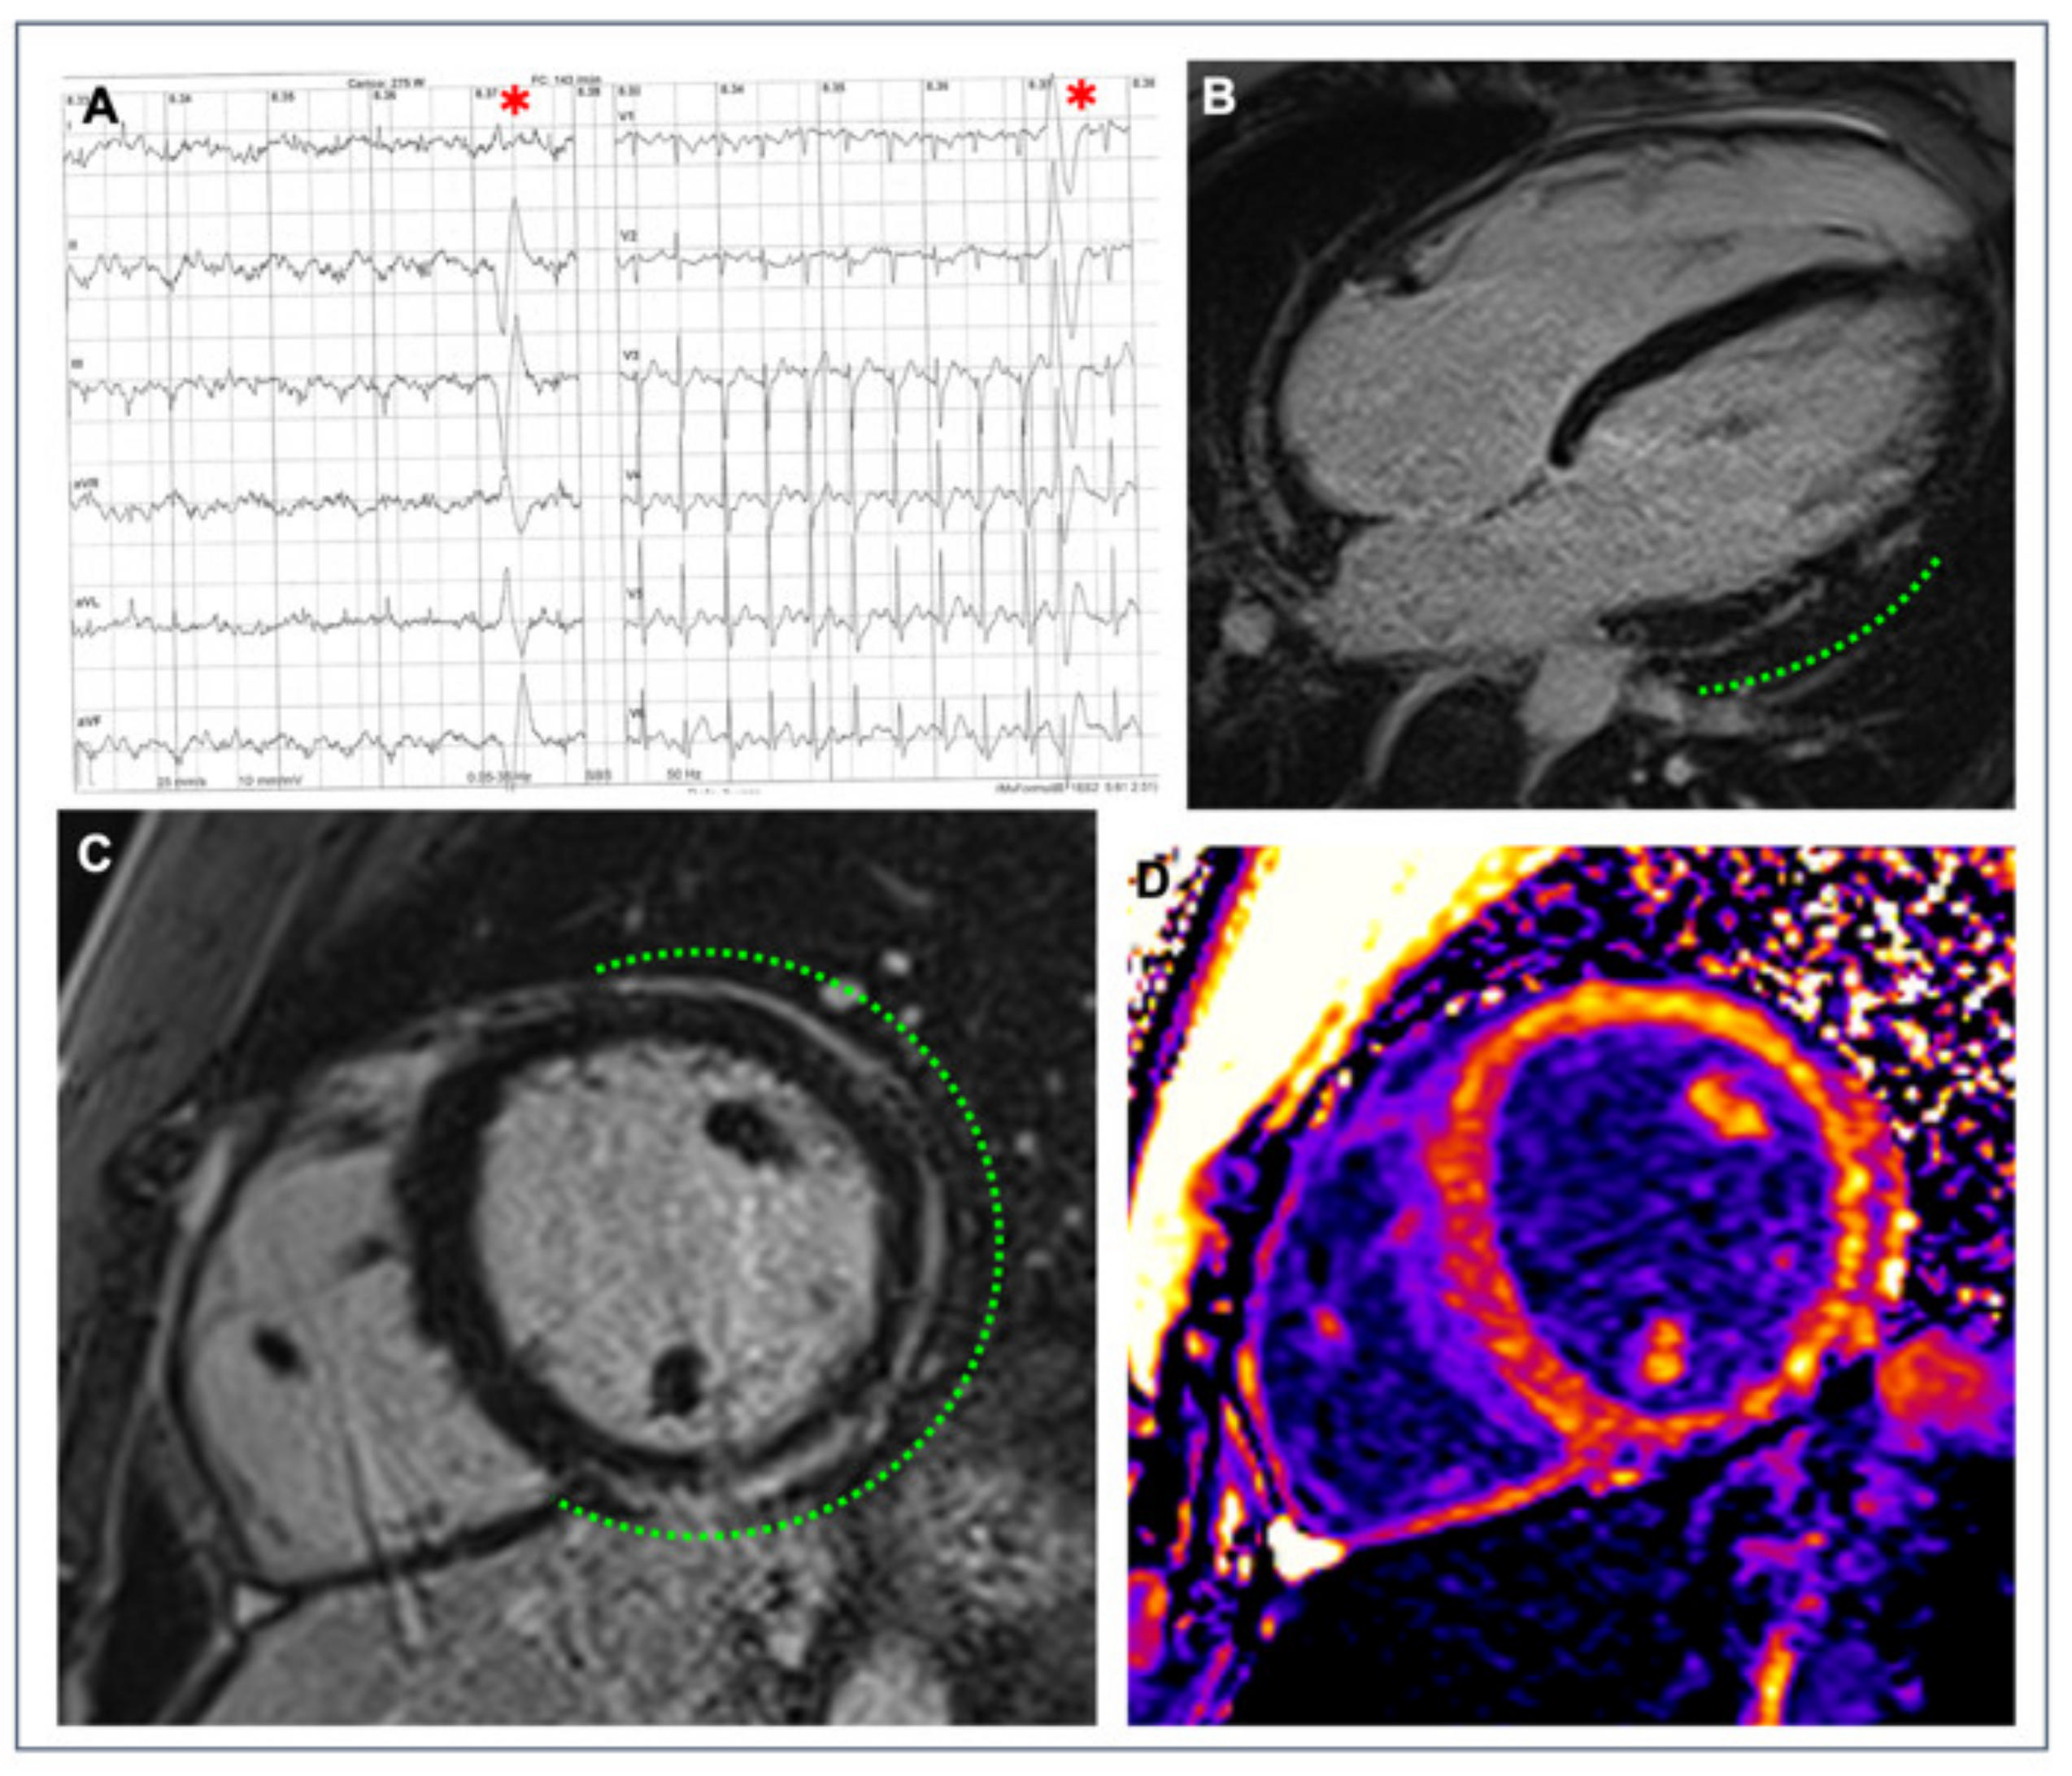

- Muser, D.; Nucifora, G.; Pieroni, M.; Castro, S.A.; Arroyo, R.C.; Maeda, S.; Benhayon, D.A.; Liuba, I.; Sadek, M.; Magnani, S.; et al. Prognostic Value of Nonischemic Ringlike Left Ventricular Scar in Patients with Apparently Idiopathic Non-sustained Ventricular Arrhythmias. Circulation 2021, 143, 1359–1373. [Google Scholar] [CrossRef]